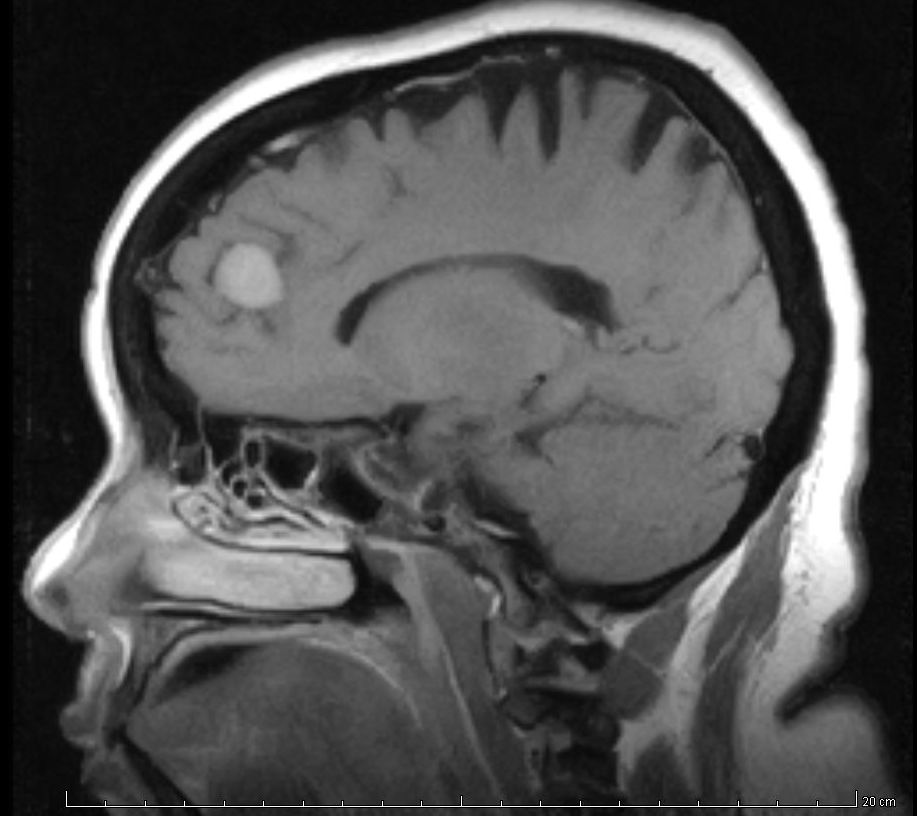

¿Qué hacer con un aneurisma cerebral pequeño que nunca sangró?

27 noviembre 2017

Con lesiones de 3 mmm o menos, descubiertas en foma incidental, la mejor estrategia parece ser no realizar tratamiento ni seguimiento rutinario con imágenes. JAMA Neurology, 20 de noviembre de 2017

Hallazgos incidentales en la resonancia magnética cerebral de niños

19 octubre 2017